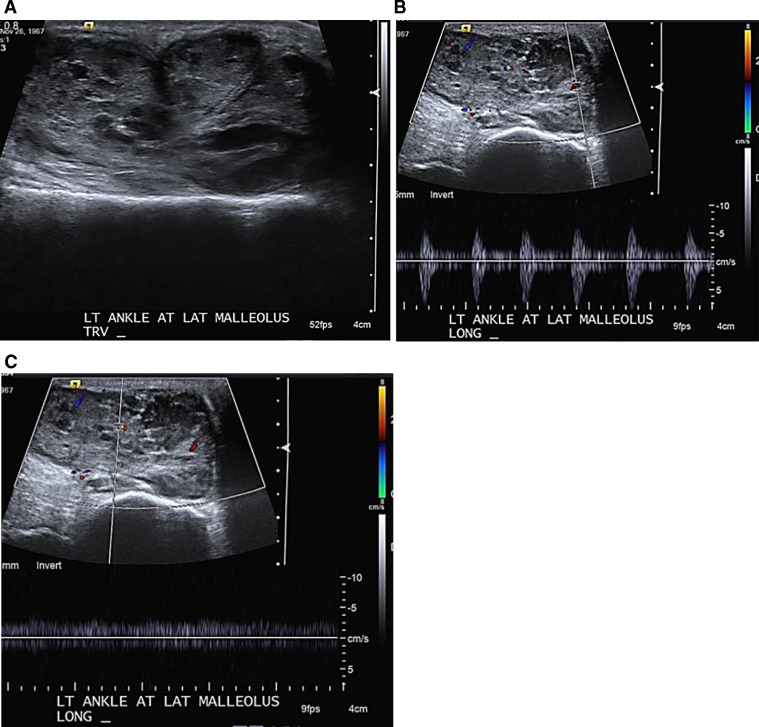

Fig. 2.

Ultrasound of the lateral ankle. (A) Grey-scale image demonstrates the lobulated contour of the lesion, with heterogeneous, internal echogenicity, not consistent with a simple ganglion or tenosynovitis. Doppler interrogation of the mass demonstrates (B) arterial and (C) venous blood flow; together indicating neovascularity, due to an inflammatory and/or neoplastic process.